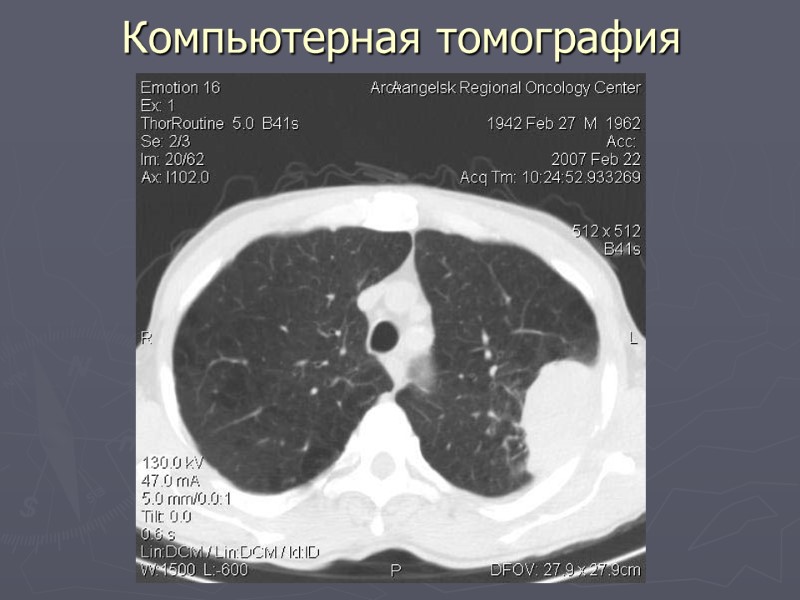

Компьютерная томография